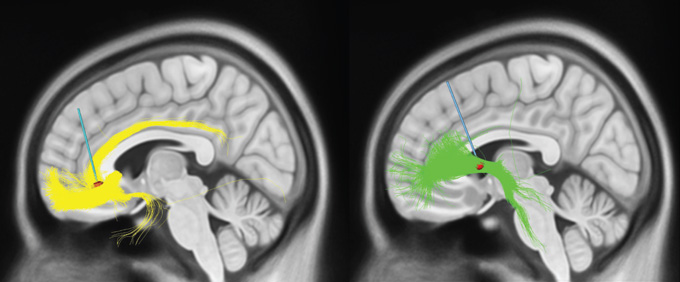

Since Broaden, and armed with better brain-imaging techniques, scientists have learned a lot more about the SCC and how it connects to other parts of the brain. The area is not a uniform glob of brain tissue; it holds a confluence of diverse white matter tracts, nerve bundles that speed information to and fro.

A recent presentation from Mayberg’s research group described the outcomes of about 50 patients from the Broaden trial, people who continued to be stimulated and monitored after the trial officially ended. It turns out that the people who got better had their electrodes implanted in a fortuitous spot in the SCC, one that hit four key white matter tracts. “It was really about targeting,” Mayberg says.

But Mayberg and her colleagues at Mount Sinai aren’t the only people conducting trials on DBS for depression, nor is their target the only one under consideration. Another promising target, called the ventral capsule/ventral striatum, or VC/VS, is more involved in feelings of reward. Stimulating there may be turning up the positive as opposed to dialing down the negative. Its connections to other brain regions are extensive, perhaps even more numerous than the SCC’s.